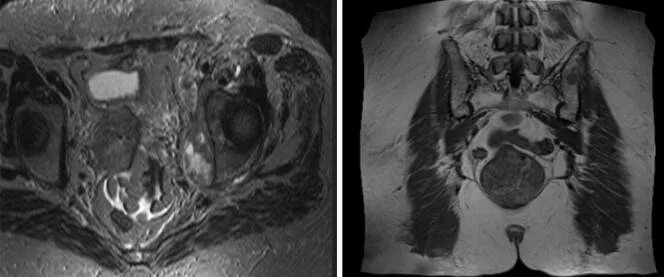

Мрт открытого типа малый таз